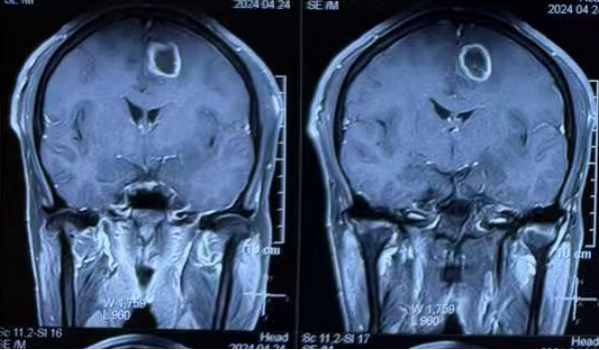

“胶质母细胞瘤”作为一种极其恶性、生长迅速的脑肿瘤,术后的治疗方案对于患者来说至关重要。术后,高女士家属得知树兰(济南)医院神经肿瘤科陶荣杰教授团队在神经肿瘤领域的治疗具有丰富的经验,随即慕名前往。复查影像结果显示:术后肿瘤仍有残留。

![]()

(图3、图4:术后1月:肿瘤残留)